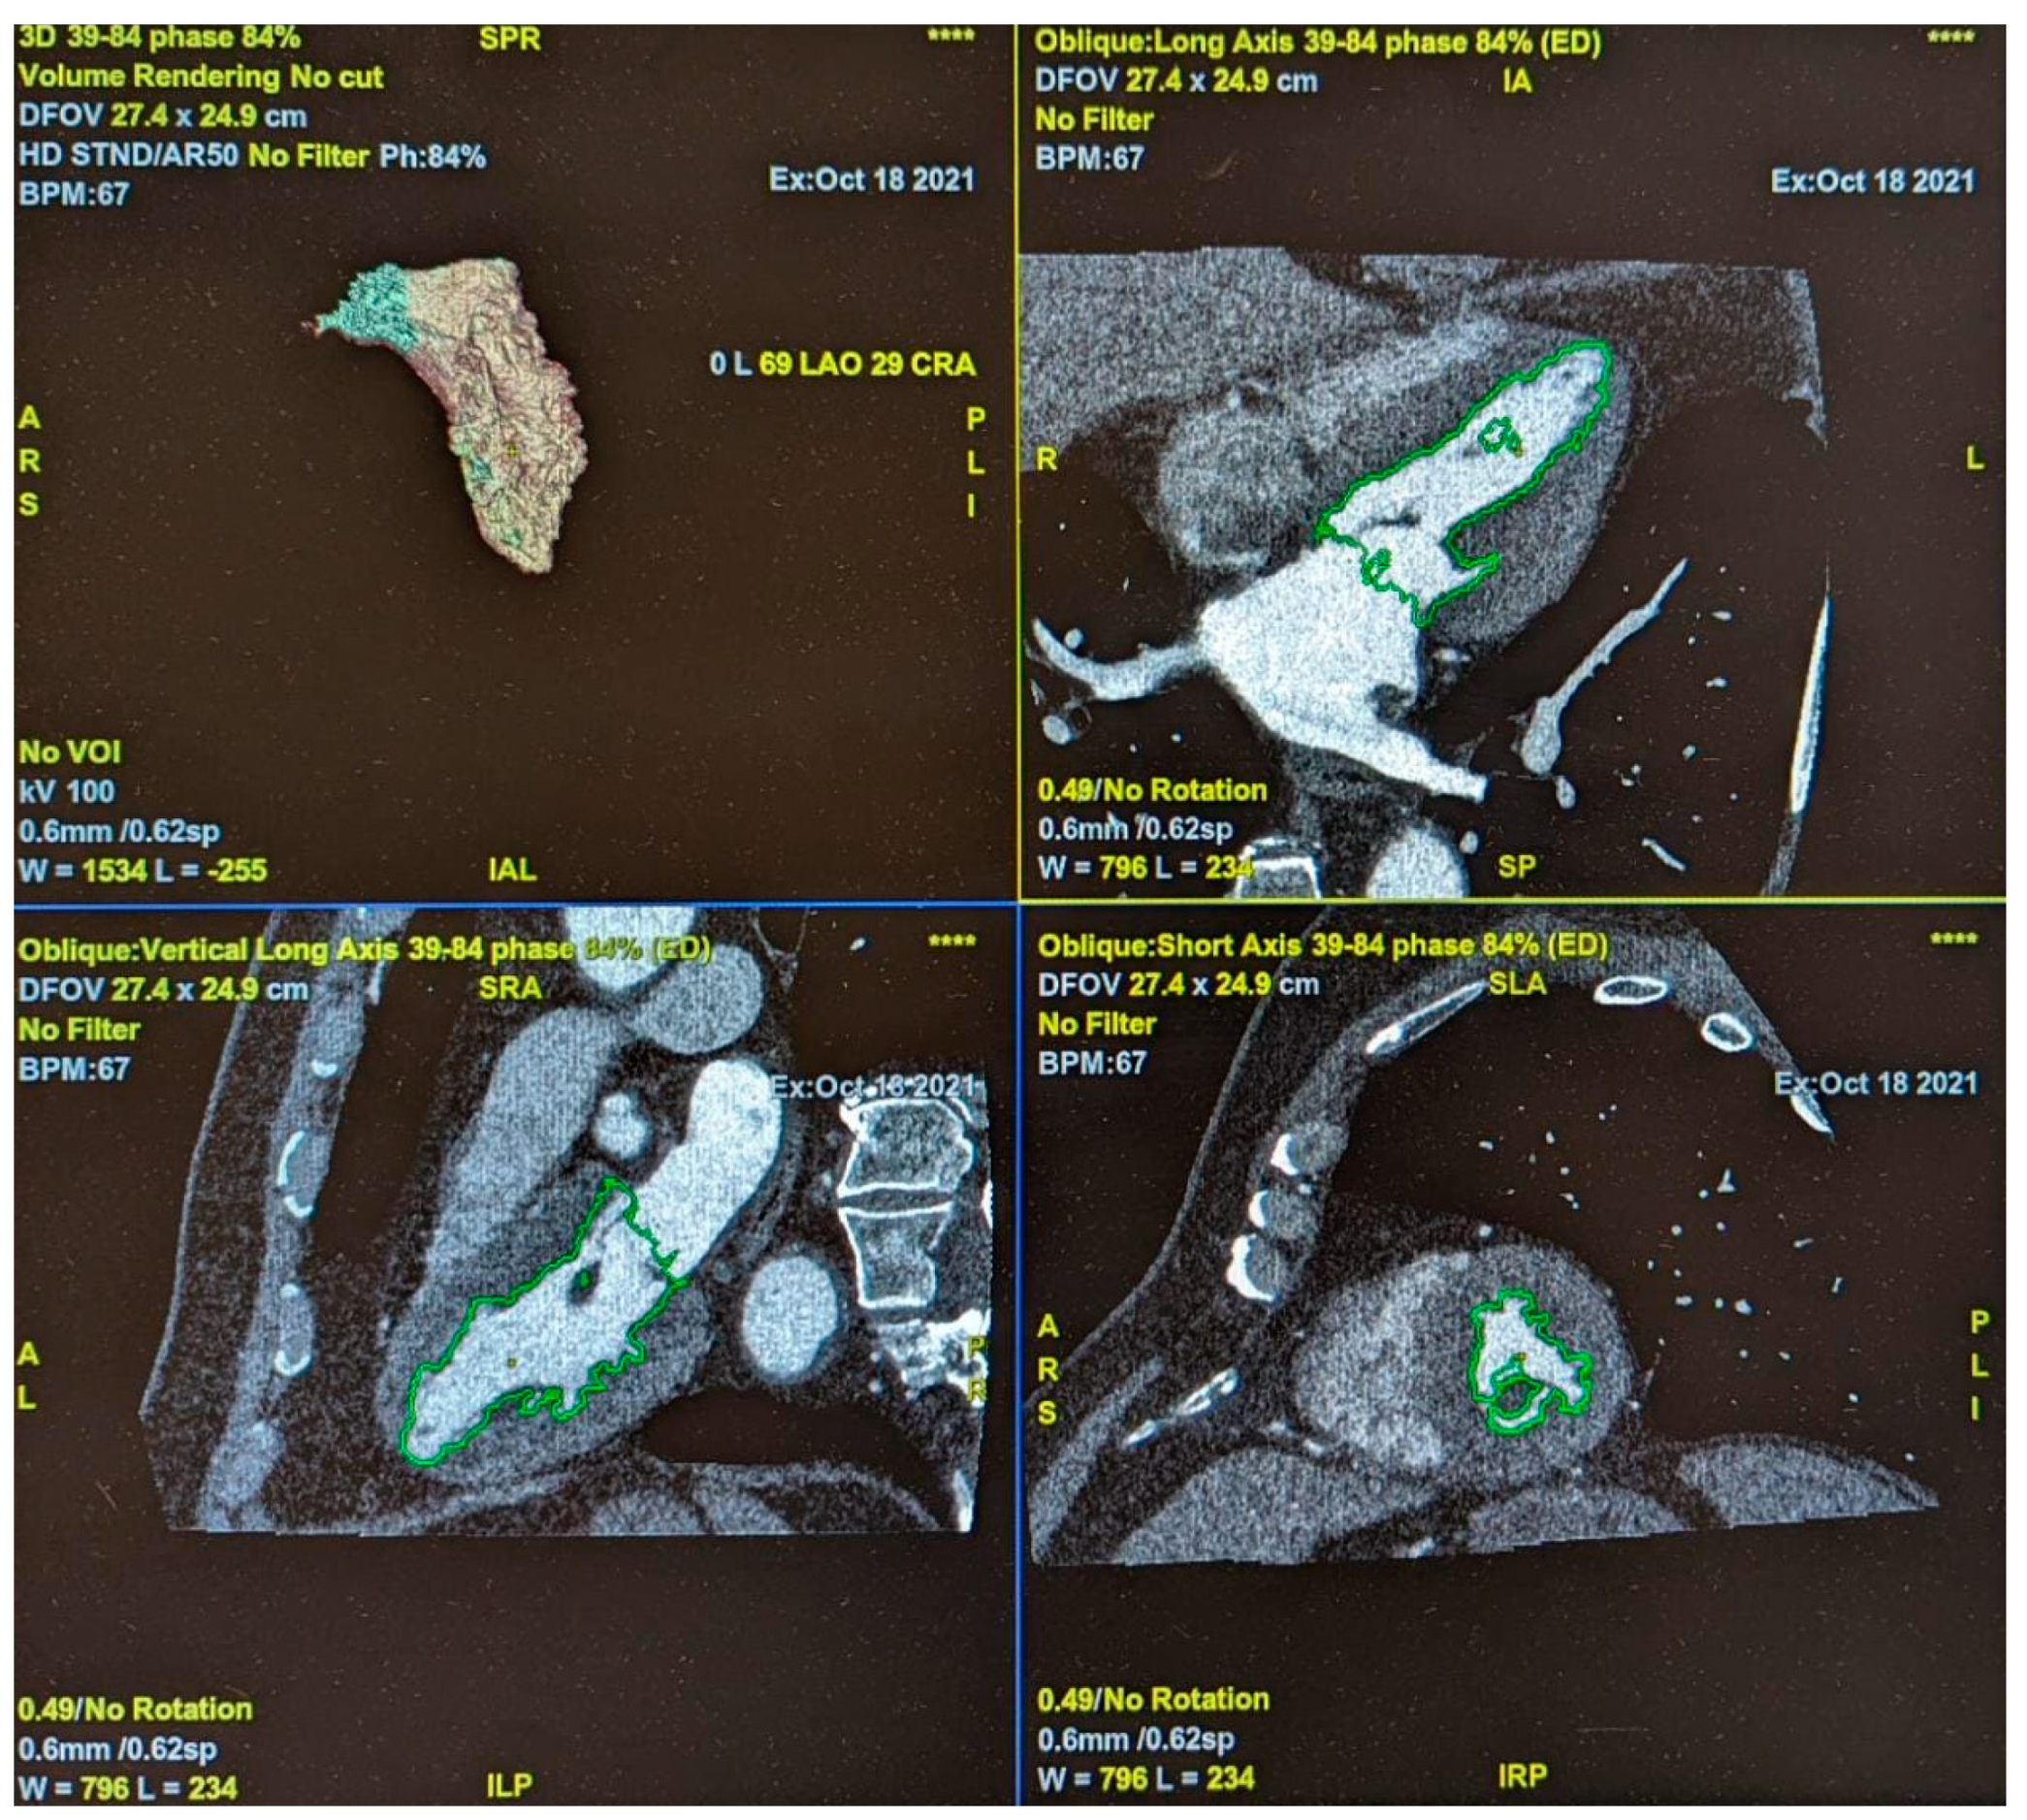

2.5. Epicardial Adipose Tissue Density

2.6. Cardiac Function